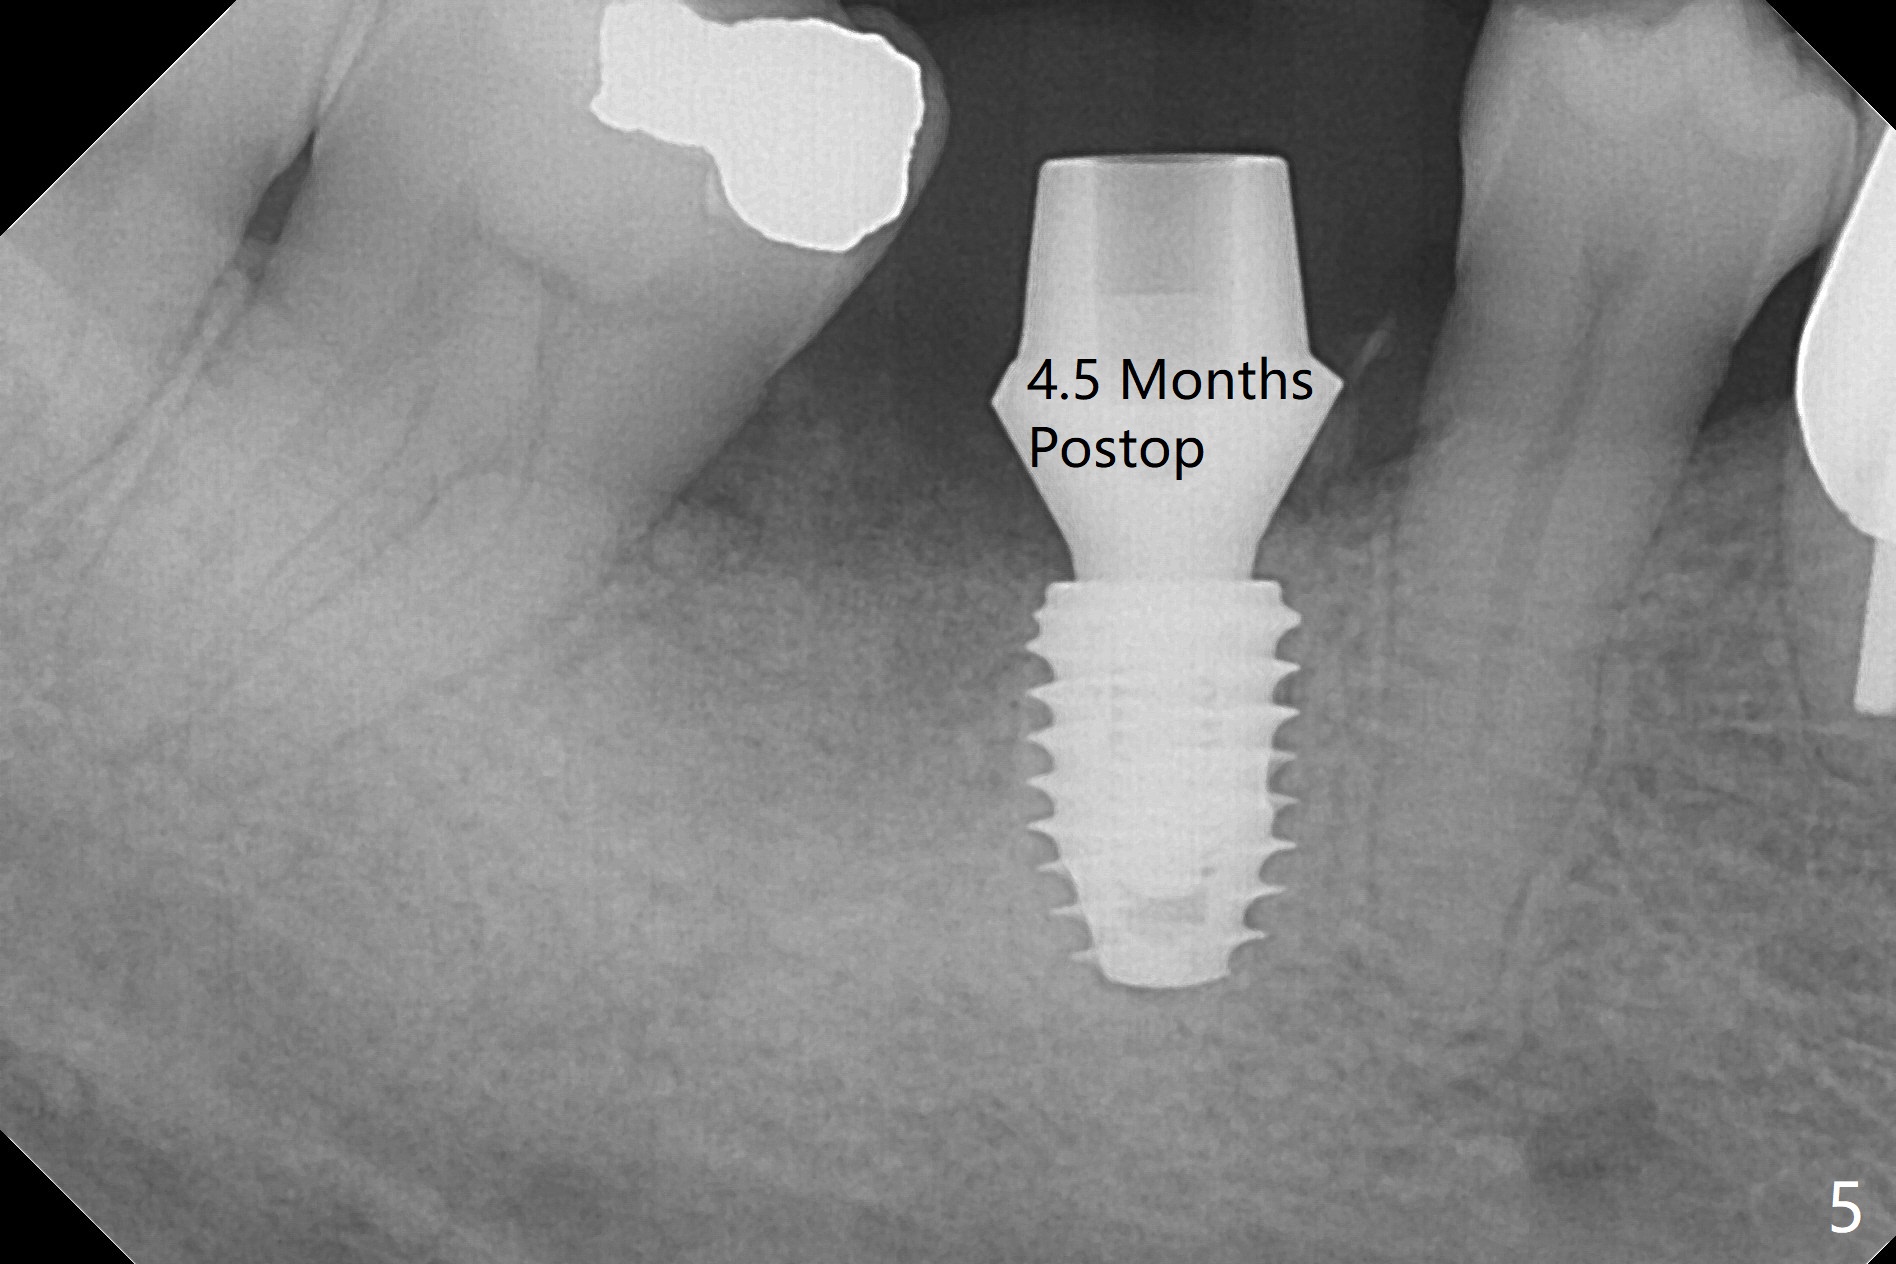

In spite of severe bone loss and 1.86 mm remaining bone after extraction of the tooth #30, a 5x7.3 mm implant achieves insertion torque of 35 Ncm with an immediate provisional (Fig.1). Periodontal dressing is applied for additional fixation of the bone graft (*) and Osteogen plug (P). Although the implant is placed in the mesial socket, the coronal end of the abutment is in the middle of the edentulous area. The patient is extremely pleased with no pain surgery. There is no postop paresthesia. The periodontal dressing (Fig.2 D) remains in place and buccal to the temporary crown (T) 10 days postop. When the former is removed, there is a gap between the margin of the provisional and that of the gingiva (Fig.3 between arrow and arrowhead), suggesting that the latter has shrunk postop. If there were no periodontal dressing, some of bone graft may have been lost. The distal socket heals when the immediate provisional is removed for revision 5 weeks postop (Fig.4). With gingival retraction cords, the abutment margin is prepared 2 months postop, particularly distal, to reduce food impaction in the future. If there is no abutment screw loosening with final restoration, it suggests that computer designed trajectory is acceptable. The implant plateau seems to be covered by the bone 4.5 months postop (Fig.5). In fact the mesiobuccal margin of the abutment is close to the corresponding crestal bone. The gingiva looks healthy 5 months postop (immediately before cementation, Fig.6), although MO amalgam of the tooth #31 is breaking down (*). Return to Lower Molar Immediate Implant, Prevent Molar Periimplantitis (Protocols, Table), Trajectory Xin Wei, DDS, PhD, MS 1st edition 04/17/2019, last revision 09/14/2019